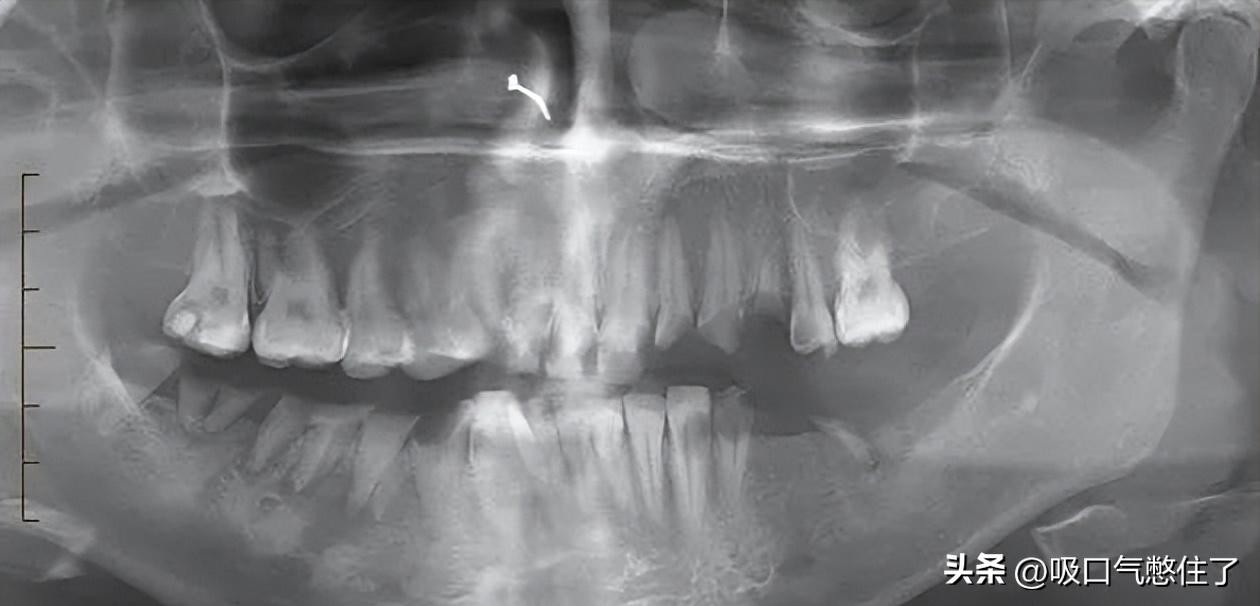

图2 患者,女,25岁,静脉注射冰毒使用者。

右下颌骨和前臼齿周围肿胀和疼痛。口腔全景图显示龋齿影响口腔的四个象限。多颗牙齿断裂或缺失,尤其是左下颌骨。右下颌前磨牙周围的透明感与脓肿形成相符。